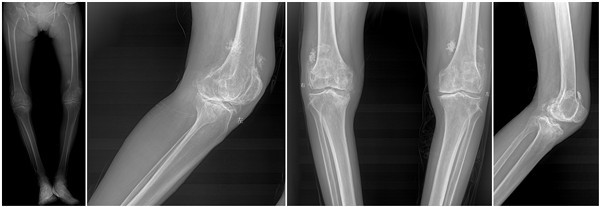

65岁郭女士10年前开始双膝关节疼痛,病情反复,半年前双膝关节疼痛加重,持续性疼痛,休息后无缓解,行走约100m左右即感疼痛难忍,不能继续行走,患者十分痛苦,生活不能自理。近日以“双膝关节疼痛10年余,加重并活动受限半年”主诉来骨一科就诊入院。经入院查体:双膝关节屈曲内翻畸形,膝内侧压痛明显,髌骨摩擦试验阳性,浮髌试验阴性,双膝关节屈伸活动受限,左侧屈曲挛缩15°,内翻25°;右侧屈曲挛缩20°内翻30°。诊断为:双膝关节骨关节炎,拟行“双膝关节置换术”。

患者术前X光片